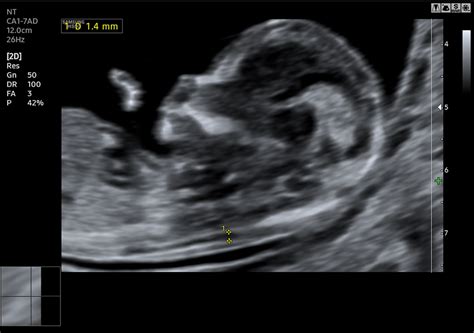

A szívburok magzati korban történő vizsgálatának elsődleges célja a veleszületett szívhibák kiszűrése már méhen belül. A speciális ultrahangvizsgálattal, többféle metszeti síkból rekonstruálva a szívet, az összetett szívhibák döntő hányada felismerhető. A szív fejlődése az intrauterin élet harmadik hetében indul meg, és ez egy bonyolult folyamat. A szív fejlődési rendellenességei a leggyakoribb veleszületett rendellenességek közé tartoznak, körülbelül minden 100 újszülöttből egyet érintenek. Hazánkban a veleszületett szívhibák előfordulása 1%.

A vizsgálat a terhesség 19-22. hete között optimális, ekkorra a szív már megfelelő méretűvé fejlődik a részletesebb vizsgálathoz. Bizonyos magas rizikójú esetekben korábbi, akár a 13-14. hét között elvégzett szívultrahang is segíthet a súlyos fejlődési rendellenességek korai felismerésében.

A magzati szívultrahang vizsgálatával a szívhibák jelentős része felismerhető. A normálistól eltérő képletek akár már a szülészeti szűrővizsgálatok során is gyanút kelthetnek, és további, speciális vizsgálatokkal lehet felállítani a pontos diagnózist. Az enyhébb, keringési zavart nem okozó rendellenességek méhen belül általában nem diagnosztizálhatóak.